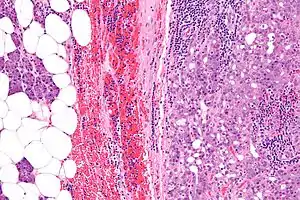

| Micrograph of an acinic cell carcinoma (right of image) and acinar glands (parotid gland - left of image). H&E stain. | |

Basophilic, bland cells similar to acinar cells. Growth pattern: solid - acinar cells, microcytic - small cystic spaces mucinous or eosinophilic, papillary-cystic - large cystic lined by epithelium, follicular - similar to thyroid tissue.

These tumors, which resemble serous acinar cells, vary in their behavior from locally aggressive to blatantly malignant.

Very high mag.